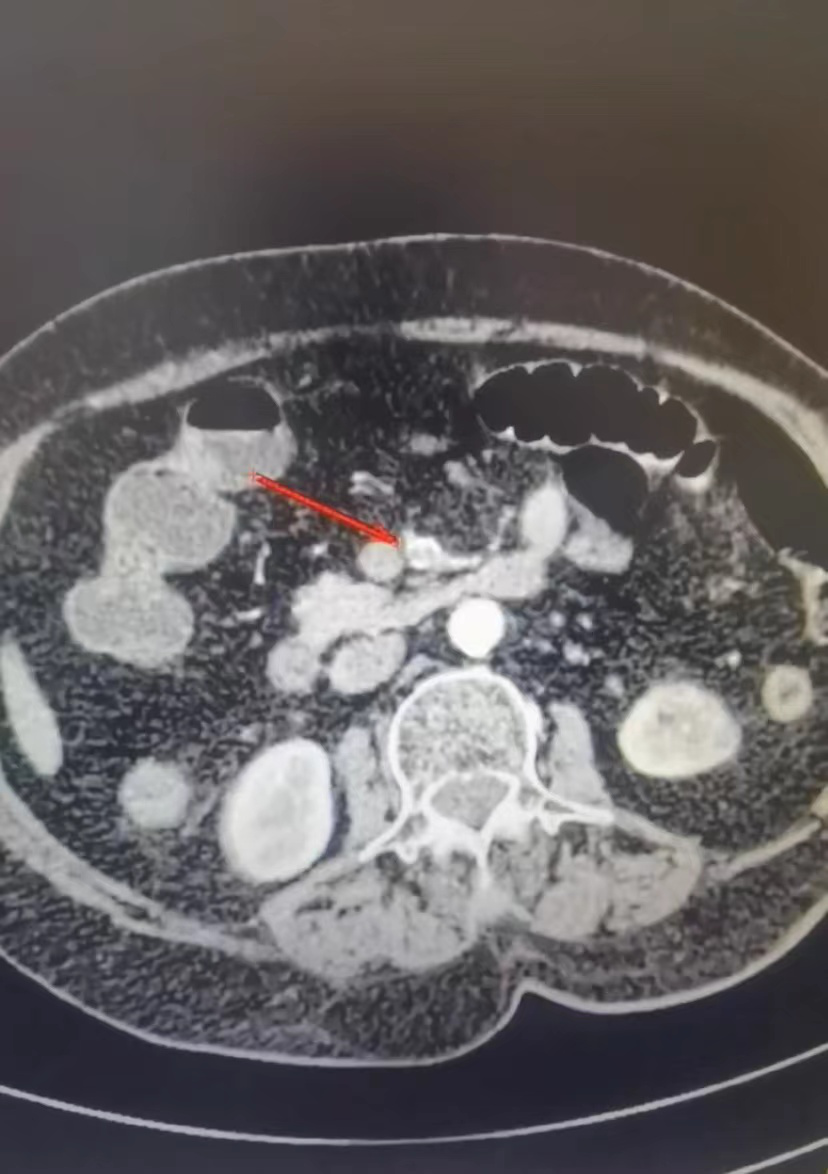

据悉,该患者为女性,现年90岁,因“腹痛17小时”,于2月5日入住新平县总医院北院区消化内科,完善相关检查后考虑为“急性胰腺炎”,经抑酸、抑制胰液分泌、抗感染等对症支持治疗,入院后第三天复查,患者胰腺炎指标均有所好转,但患者仍有阵发性腹痛加剧的情况,予以患者腹部增强CT检查,结果回报提示患者存在肠系膜上动脉中段混合性斑块,管腔重度狭窄、局部闭塞。因肠系膜上动脉为小肠主要供血动脉,闭塞后可导致小肠缺血,从而出现腹痛,若不及时治疗,缺血进一步加重将会导致小肠缺血性坏死,危及患者生命。由于患者年龄大,手术风险巨大,为彻底治愈患者,改善患者生活质量,北院区消化内科紧急联系西院区骨伤科,开展两院区多科会诊。北院区消化内科与西院区骨伤科充分评估患者病情后,决定采用最新微创介入置管溶栓术为患者进行精准手术治疗,该手术方式对手术医生技术要求高,属于介入类高新技术,手术损伤小,基本无出血,不用开腹只需局部麻醉即可进行手术,避免了传统外科开腹手术和全身麻醉对超高龄患者带来的巨大风险,可以快速解除肠缺血进一步加重出现肠坏死的风险。在征得患者及家属同意后,北院区消化内科与西院区骨伤科经精心术前准备,团队共同协作在北院区介入室顺利为患者完成手术,术后继续给予患者导管内溶栓治疗,并于2月12日再次行肠系膜动脉造影评估,原栓塞段已再通,患者腹痛消上人、无出血渗血,复查凝血功能良好,治疗取得了圆满的成功!

(狭窄)

(溶栓前)

(溶栓后) “团结就是力量,协作才能攻坚克难!”本次超高龄患者肠系膜上动脉置管溶栓术的成功开展,充分发挥了新平县总医院设备人才资源共享的优势,实现了不同院区不同学科之间的多科联动和团结协作,最大限度地缩短了患者的诊断和治疗等待时间,增加了治疗方案的可选择性和个性化治疗方案的选择空间,对促进患者术后康复、改善患者预后具有极为重要的积极作用,同时避免了不停转诊、重复检查给患者家庭带来的经济负担,有力地提升了县域各族群众的就医获得感、幸福感和满意度。在今后的发展进程中,新平县总医院将秉持“人民医院为人民”的宗旨和“团结奉献、精益求精”的医院精神,牢记“爱岗敬业、勤学精术”的医院院训,树牢“敬畏生命、求实奋进”的价值观,以高度的责任感、使命感和紧迫感,脚踏实地,攻坚克难,为实现“构建技术精湛、分级诊疗合理、中西医并重的集团化现代化县域医疗共同体三级医院”的发展愿景和“大病不出县、小病不出乡、头疼脑热不出村”的医改目标,为奋力开创新平转型跨越绿色崛起新境界和高质量推进玉溪“一极两区”建设而不懈奋斗! (来源:县总医院)